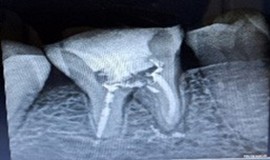

A 44-year-old woman presented to our dental department in May 2025 with a one-week history of a prominent left facial swelling extending from the corner of her mouth to the lower border of her left eyelid, accompanied by restricted eye opening. Her dental history was notable for a large amalgam restoration on tooth 26. Periapical radiography revealed an extensive radiolucent lesion associated with the palatal root of that tooth.

Figure 1: Pre operative IOPA revealing a huge periapical lesion wrt palatal root of 26.